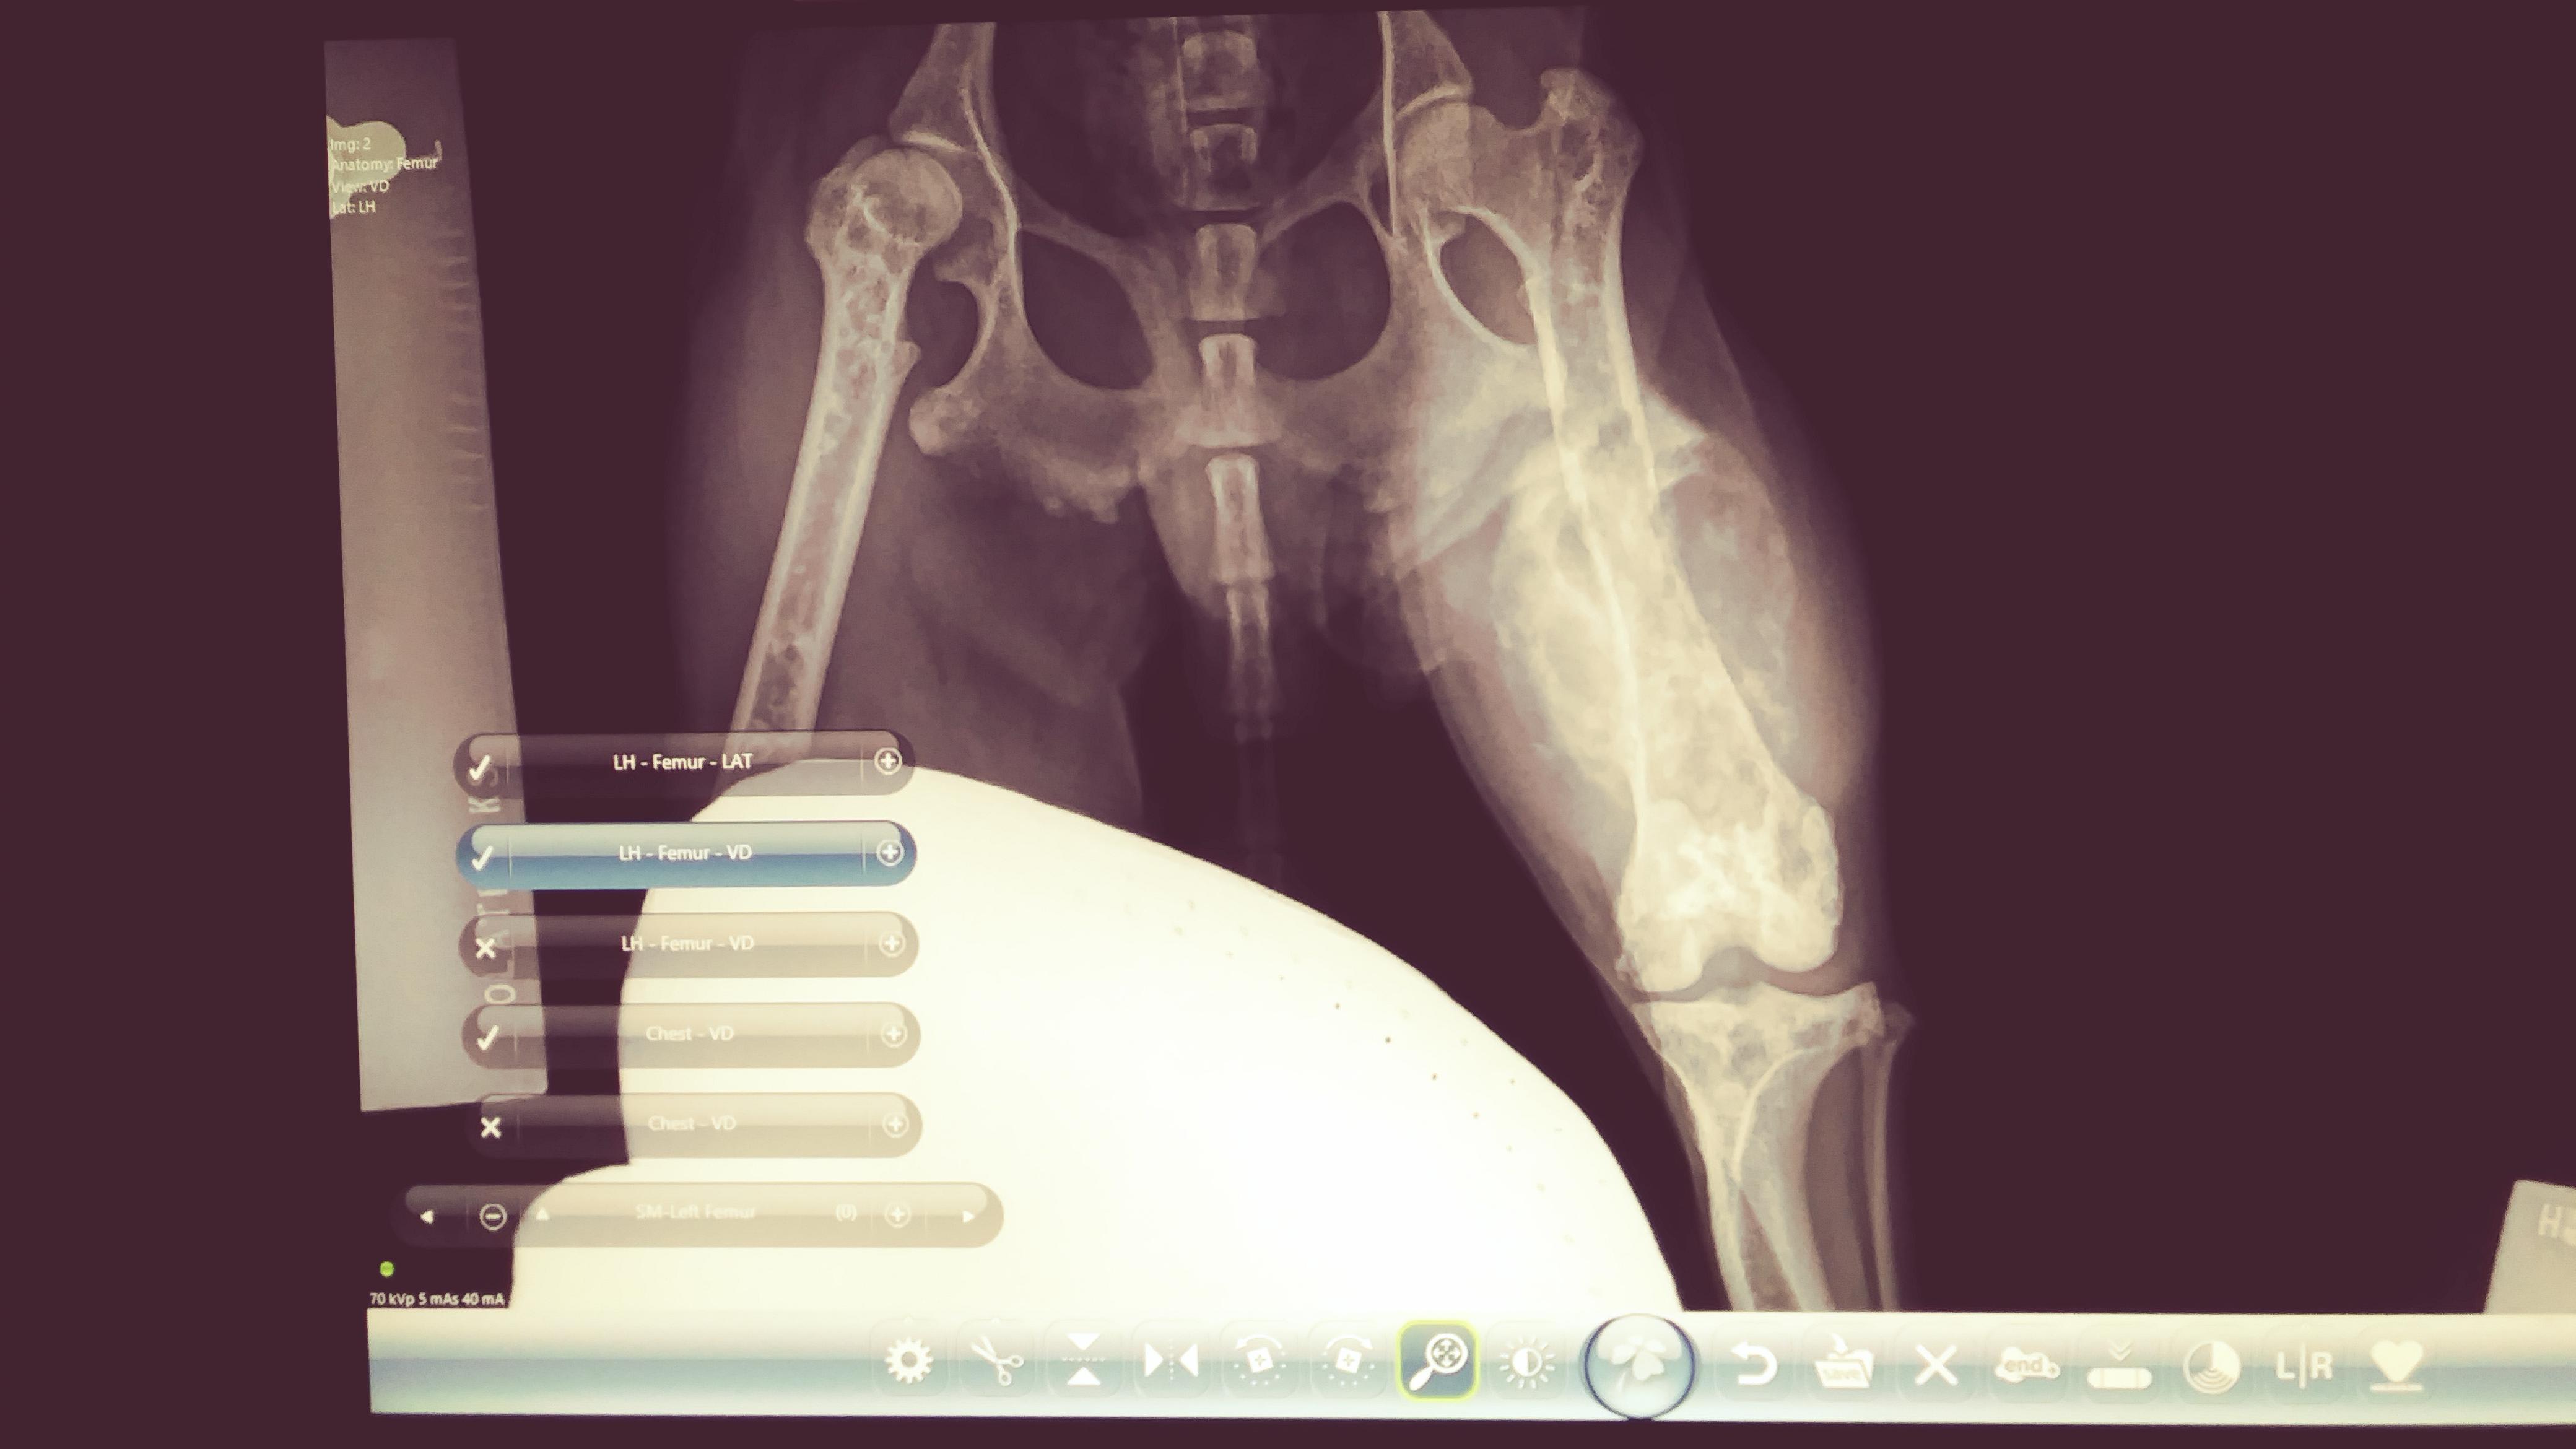

April 2018 injury to rear left leg ( no use). No condition change (3wks) brought to vet. X-rays revealed Mass on entire femur. Diagnosis, bone cancer. No biopsies or testing to confirm. Offered pain meds (narcs), refused, requested ibuprofen. Eating, drinking, playful, happy. 1 yr later annual appt. More x-rays. Femur and 1/2 pelvis gone, mass cannot be seen. Vet tests for blastomycosis/histoplasmosis, negative x2. Reverts back 2 cancer. Is a misdiag still possible?

I am so sorry to hear about your dog. My first suspicion would also be cancer and since the bone is now gone, it isn't necessarily that the mass is gone so much as the disease has eaten away all the healthy bone. At this point, I would recommend referral to a specialist who deals in oncology (cancer) or a surgeon. It may be possible to surgically remove the affected leg and then do histopathology on the tissue to get a definitive diagnosis. A needle biopsy may also be a possibility for diagnosis, but it is not a gaurantee that a good sample can be achieved this way.